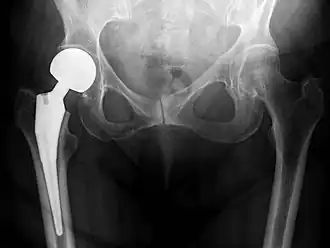

An X-ray showing a left hip (right of image) that has been replaced, with the ball of this ball-and-socket joint replaced by a metal head that is set in the femur and the socket replaced by a cup

Hip replacement is a surgical procedure in which the hip joint is replaced by a prosthetic implant, that is, a hip prosthesis.[1] Hip replacement surgery can be performed as a total replacement or a hemi/semi(half) replacement. Such joint replacement orthopaedic surgery is generally conducted to relieve arthritis pain or in some hip fractures. A total hip replacement (total hip arthroplasty) consists of replacing both the acetabulum and the femoral head while hemiarthroplasty generally only replaces the femoral head. Hip replacement is one of the most common orthopaedic operations, though patient satisfaction varies widely between different techniques and implants.[2] Approximately 58% of total hip replacements are estimated to last 25 years.[3] The average cost of a total hip replacement in 2012 was $40,364 in the United States (€37,307.44 in euros), and about $7,700 to $12,000 in most European countries. NOTE: In euros, that is from €7,116.92 to €11,091.30 euros.[4]